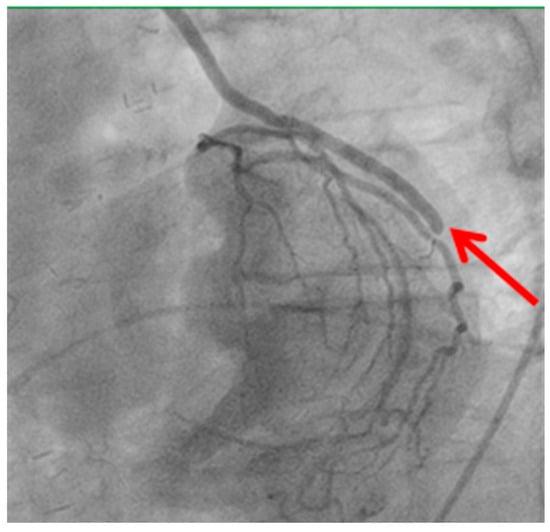

Technical issues remain a principal cause of PMI, with early graft thrombosis or occlusion being leading indications for uCAG (Figure 1, Figure 2, Figure 3 and Figure 4 illustrate typical technical causes, including proximal anastomotic stenosis, kinking, distal anastomotic stenosis, and misplaced anastomoses). Notable contributors include anastomotic stenosis, kinking, overstretching of grafts, and temporary graft spasm [,]. Prueßer et al. demonstrated that 30% of PMI cases detected via CAG were graft-related failures []. In this context, uCAG often reveals technical failures immediately post-surgery, providing the advantage of guiding targeted percutaneous coronary intervention or revascularization. Graft spasm, which can be relieved by nitrates, may also lead to acute ischemia. It refers to the temporary constriction of the bypass graft, reducing blood flow to the myocardium. This condition can be caused by various factors, including surgical trauma, inflammation, or the release of vasoactive substances [].

Figure 3.

Stenosis of distal anastomosis.

Distal anastomotic stenosis (shown by the red arrow) observed on postoperative angiography. This finding underscores the potential for technical issues at the distal anastomosis site, which may require percutaneous intervention or revision surgery.